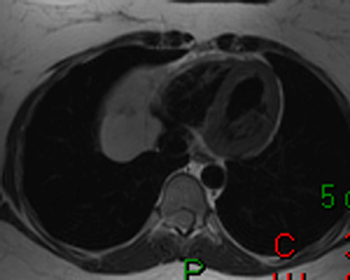

16) What aortic abnormality is seen on the T1 weighted axial image below?